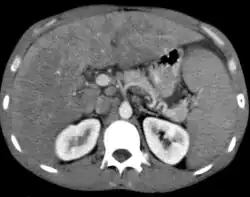

Non-Hodgkin lymphoma with hepatic involvement